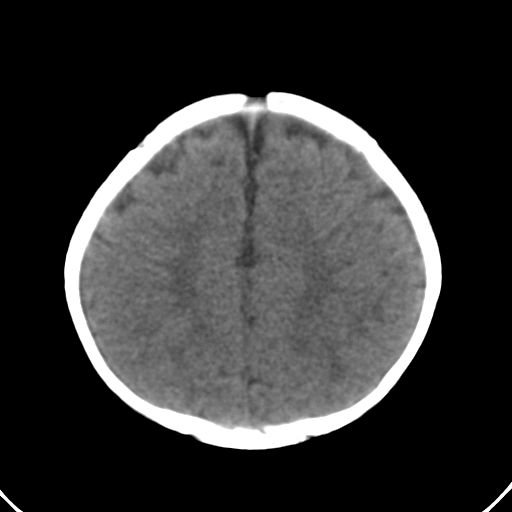

男,10月,足月剖腹产,无缺氧病史,当时评分均正常,学走路时脚后跟不着地!

小孩子片子,看得少,请各位老师看看有问题没?

未见明显异常。

外部性脑积水

考虑外部性脑积水

轻度脑外脑积水表现.